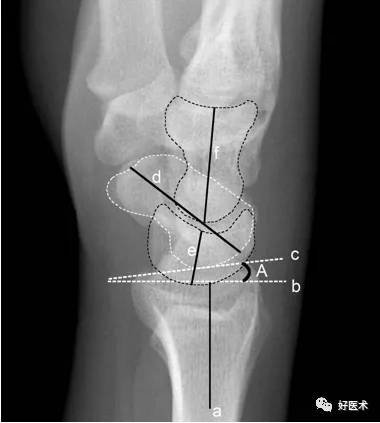

測量方法

a.橈骨縱軸線 b.橈骨縱軸線垂線 c.橈骨遠端關節面切線 d.尺骨遠端關節面水平線

A.橈骨內傾角 B.橈骨莖突長度 C.尺骨莖突長度

A.正常為15~35˚ 。若此角度改變,提示橈骨遠端骨折或腕關節脫位。

B.正常為8~18mm,且橈骨莖突較尺骨莖突低1~1.5cm。若此長度改變,提示橈骨遠端骨折。

C.正常為2~8mm。若此長度改變,提示尺骨莖突骨折或尺骨莖突過長(尺骨莖突撞擊綜合症)

a.舟骨、月骨切線 b. 月骨三角骨切線 c.尺骨遠端關節面切線 d.腕骨總高度 e.頭狀骨長度

A.腕骨角 B.尺腕角

A.約130°。腕關節骨折、脫位時此角增大,此角減小見於Madelung畸形和卵巢發育不全。

B.正常為21~51˚。若此角度改變,提示腕骨骨折或腕關節脫位。

*腕骨高度指數:d與第3掌骨長度的比值,正常範圍0.54±0.03。Nattrass腕骨高度指數為d/e,正常範圍1.57±0.05。在月骨缺血壞死、不穩定型舟骨骨不連、腕關節不穩時,腕骨高度指數減小。